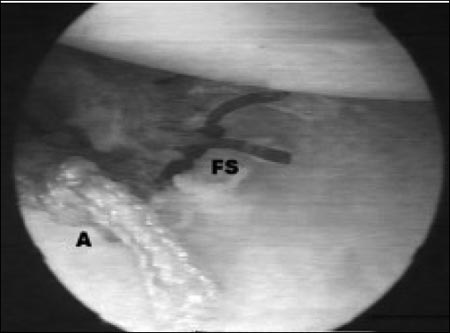

Figura 1: C: cánula - FS: (free suture) sutura libre Fijación de la sutura libre en la parte antero-inferior de la cápsula*

*Para que se comprenda mejor, hemos puesto solo una en la figura, pero nosotros usualmente usamos tres.